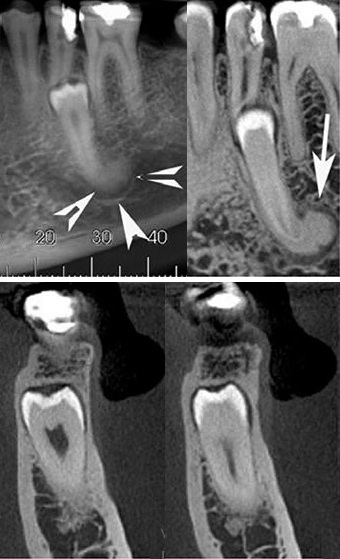

Cone-beam CT phantom of the maxillofacial region showing teeth, alveolar bone, sinuses, nasal cavity, and mandibular...

Dental phantom showing common pathology: carious lesions, periapical abscess, root resorption, and a metallic restoration